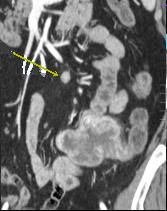

Leiomyosarcoma de grand

taille de ileon et nodule metastatique ganglionaire

a distance ( fleche jaune ) . |